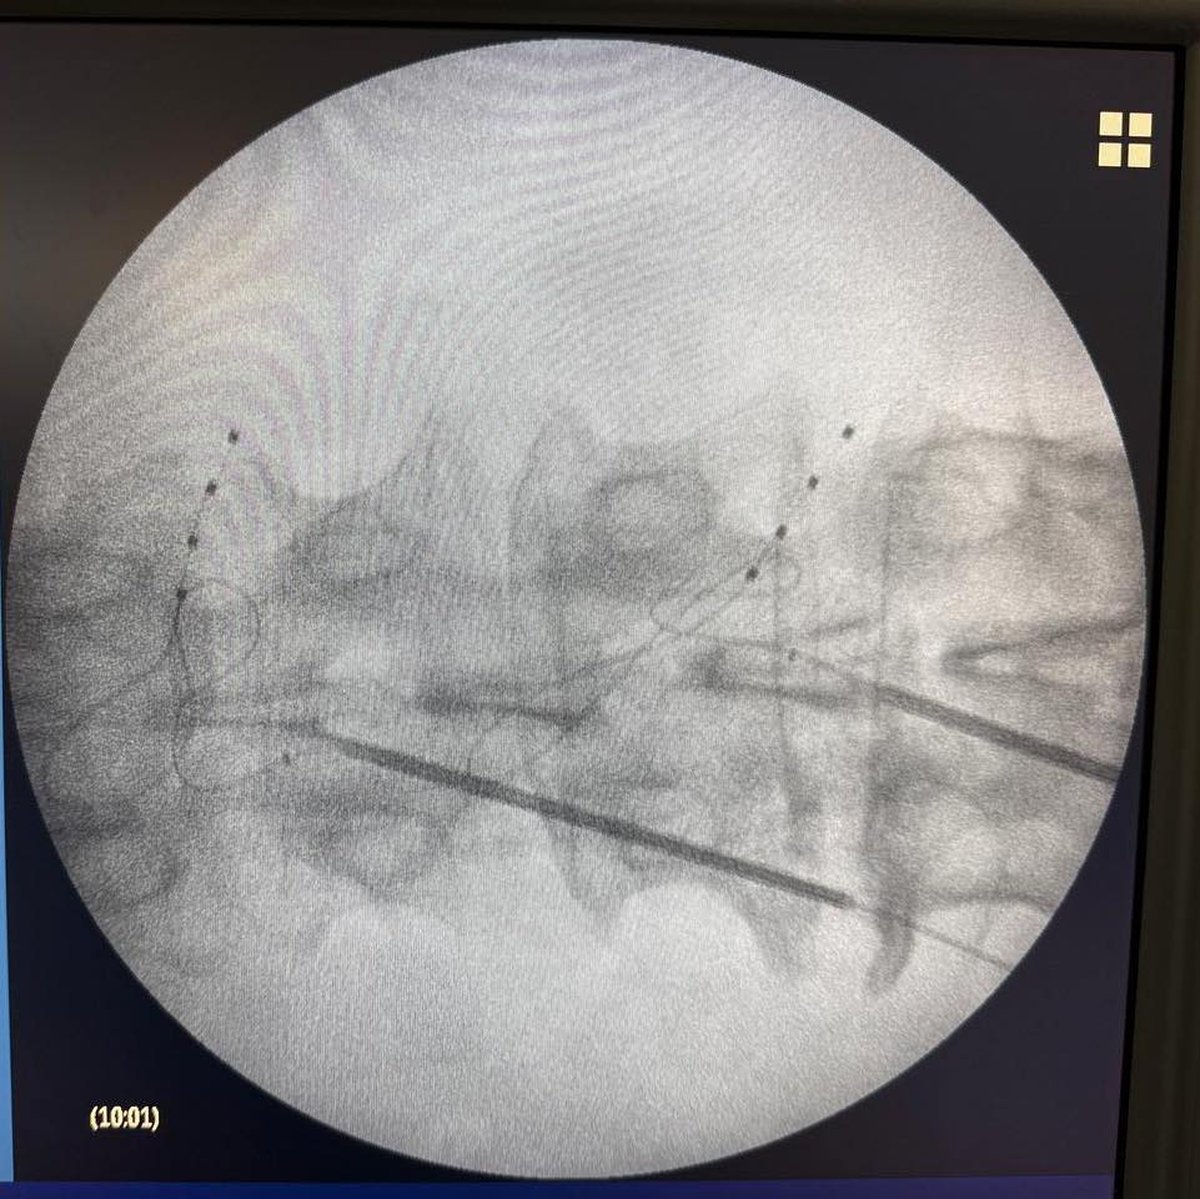

Se trata del implante de un neuroestimulador en el ganglio de un paciente que sufría un fuerte dolor crónico en la zona de la raíz dorsal y cuya cirugía se encaró bajo la tutela del equipo de neurología del nosocomio público, el cual fue encabezado por el Doctor Juan Pablo Casasco.

Tal intervención quirúrgica consiste en la colocación de dicho dispositivo para que envíe impulsos eléctricos al sistema nervioso y ayudar a que evite las molestias bloqueando las señales que se mandan al cerebro (similar a cómo actúa un marca pasos), permitiendo que se lo adapte a las necesidades de cada persona.